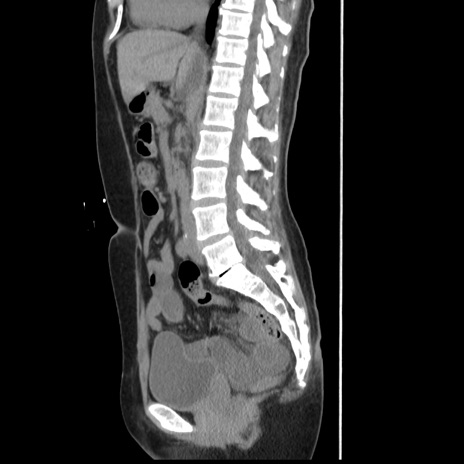

横断像

冠状断像